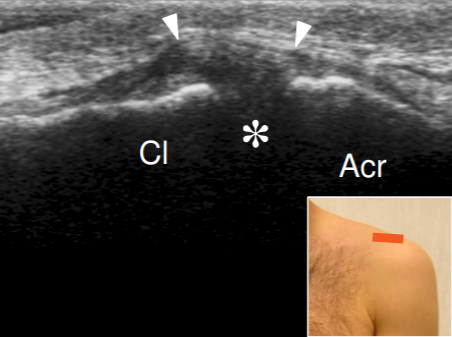

Articulation acromio-claviculaire

- Coupe axiale